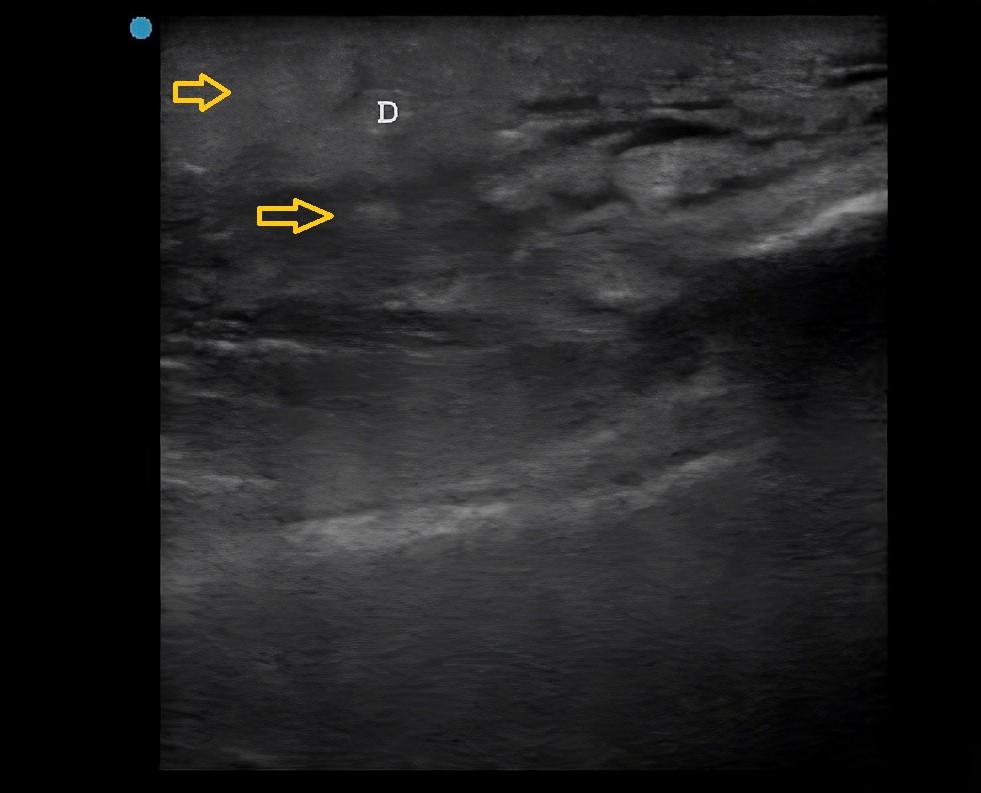

Figura 2. Ecografía musculoesquelética y de partes blandas de la región lateral del tercio distal del miembro inferior derecho. Se aprecia edema subcutáneo alrededor de los lobulillos (patrón “en empedrado” o cobblestoning) (flechas amarillas).